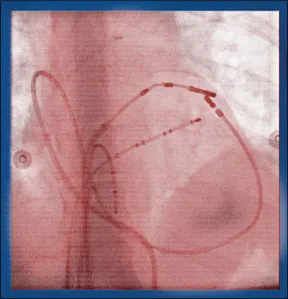

For patients with atrial fibrillation (AFib), a condition in which the heart beats irregularly, medication can often return the heart to its normal rhythm. But when medication is ineffective, AFib may require ablation-a procedure that entails going into the heart and stopping the abnormal electrical impulses that create the irregular heartbeat. The most common method of performing this procedure is called catheter ablation, in which a catheter-a thin, flexible tube-is threaded to the heart through the femoral vein via a small incision in the leg or groin. However, for patients who are not candidates for the procedure or in whom it is not succesful, another method called epicardial ablation is emerging as an alternative. "Patients with left atrial enlargement, long-standing persistent AFib, and anatomic barriers like abnormal veins in the leg are good candidates for epicardial ablation but not catheter ablation," says Marc Gillinov, MD, a cardiac surgeon at Cleveland Clinics Heart & Vascular Institute. "While epicardial ablation is performed on a small percentage of people with AFib, its a small percentage of a large number of people who otherwise have no treatment options."